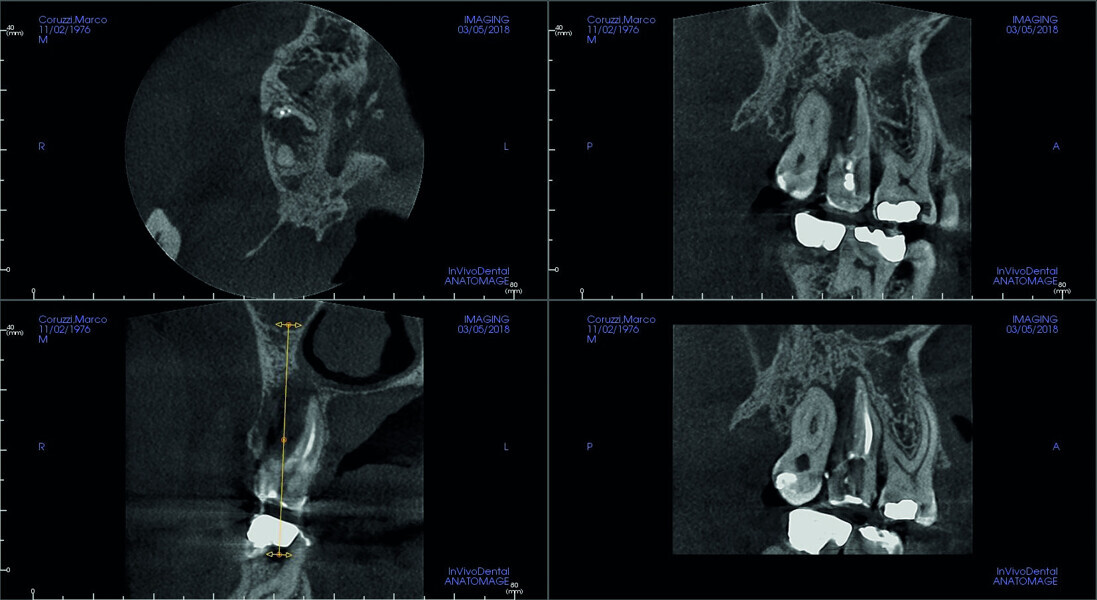

Fig. 5: Pre-op CBCT scan, sections.

Fig. 6: Pre-op CBCT scan, detailed section of the maxillary second molar.

Fig. 7: Pre-op CBCT scan, coronal and sagittal views.